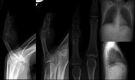

Multifocal chondrosarcoma of the hand: Case report and review of the literature

Few multifocal hand chondrosarcomas have been reported. To our knowledge, this report is the first to describe multifocal hand chondrosarcoma in a patient with no evidence of prior enchondroma, Ollier's disease, or Maffucci syndrome.